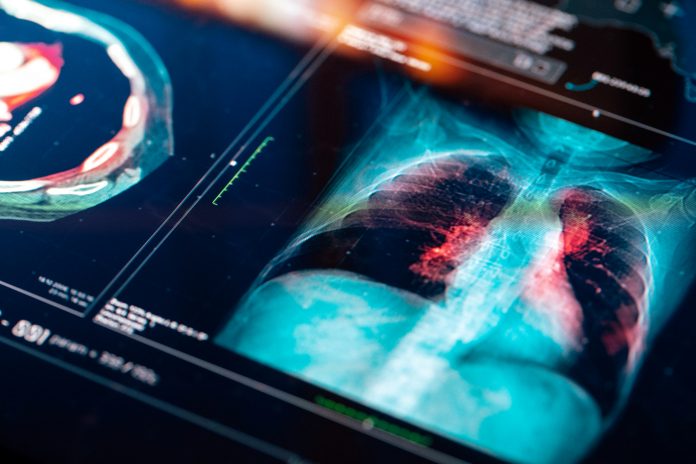

Researchers have identified 140 genes that could change how non-small cell lung cancer (NSCLC) patients are treated with lung cancer immunotherapy and low-dose radiation

Published in Cell Reports Medicine on Feb. 23, immunotherapy, a treatment using the body’s immune system to combat cancer, has offered hope to many lung cancer patients.

However, its effectiveness has been limited, with only 20 to 25 per cent of individuals responding positively. This new study addresses this challenge by identifying a genetic signature that could predict enhanced disease-free survival among NSCLC patients undergoing combination therapy.

The study, led by a team of researchers, looked into the complexities of NSCLC treatment by examining a cohort of 60 patients. Initially, the researchers discovered that combining low-dose radiation with durvalumab, an immune-boosting drug, significantly improved cancer-free survival rates. Building on this, the team aimed to solve why certain tumours failed to respond to this therapy.